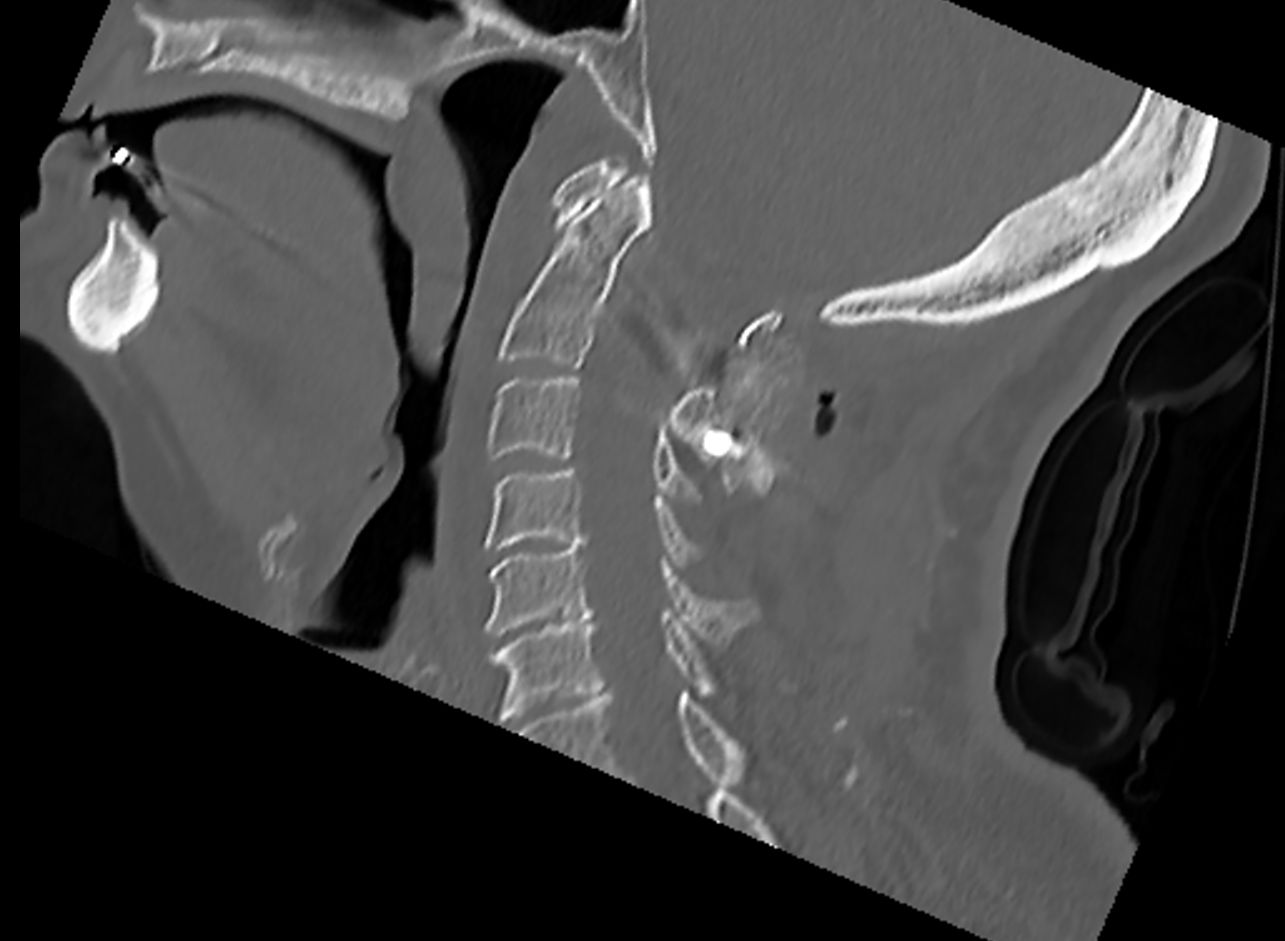

• Zlomenina dens axis (obratel C2), která je typická ve starším věku. Ošetření pomocí zadní stabilizace.

Jednotlivé procedury se při operačním výkonu prolínají a fungují společně. Pro zajištění primární pooperační stability ze zadního přístupu používáme v krční i torakolumbální oblasti vnitřní fixátory. Jejich součástí jsou šrouby případně háky a spojovací tyče překlenující poraněný páteřní segment. Z předního přístupu jsou nejčastěji aplikovány kostní štěpy nebo klece přemostěné dlahou v krční oblasti, expandibilní klece a fixátory v torakolumbální oblasti. Všechny fixační prvky jsou vyrobeny ze slitiny titanu, která omezuje negativní stíny na vyšetření CT a jsou MR kompatibilní. Pro dosažení trvalé kostní stability používáme přemostění poraněného obratle nebo obratlů kostními štěpy z lopaty kosti kyčelní nebo syntetickou náhradu (trikalciumfosfát, hydroxiapatit).